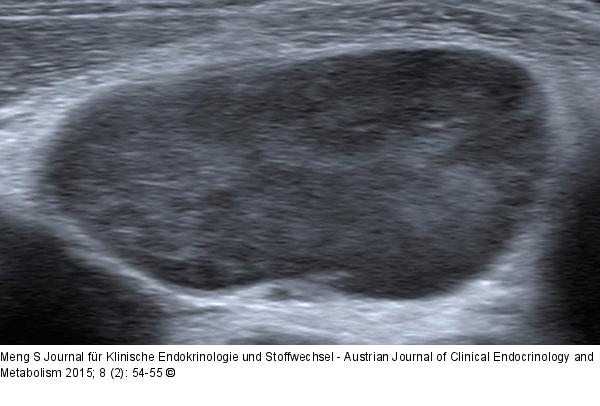

Abbildung 7: Ultraschall-Lymphknoten Homogenitätsverlust der Binnenstruktur. Scheinbar homogene, nahezu echoleere und somit zystisch erscheinende Lymphknoten können bei entsprechender Einstellung der Geräteparameter eine mikronoduläre Struktur aufweisen. Dies ist typisch für Lymphome. „Small lymphocytic lymphoma“ (SLL). |